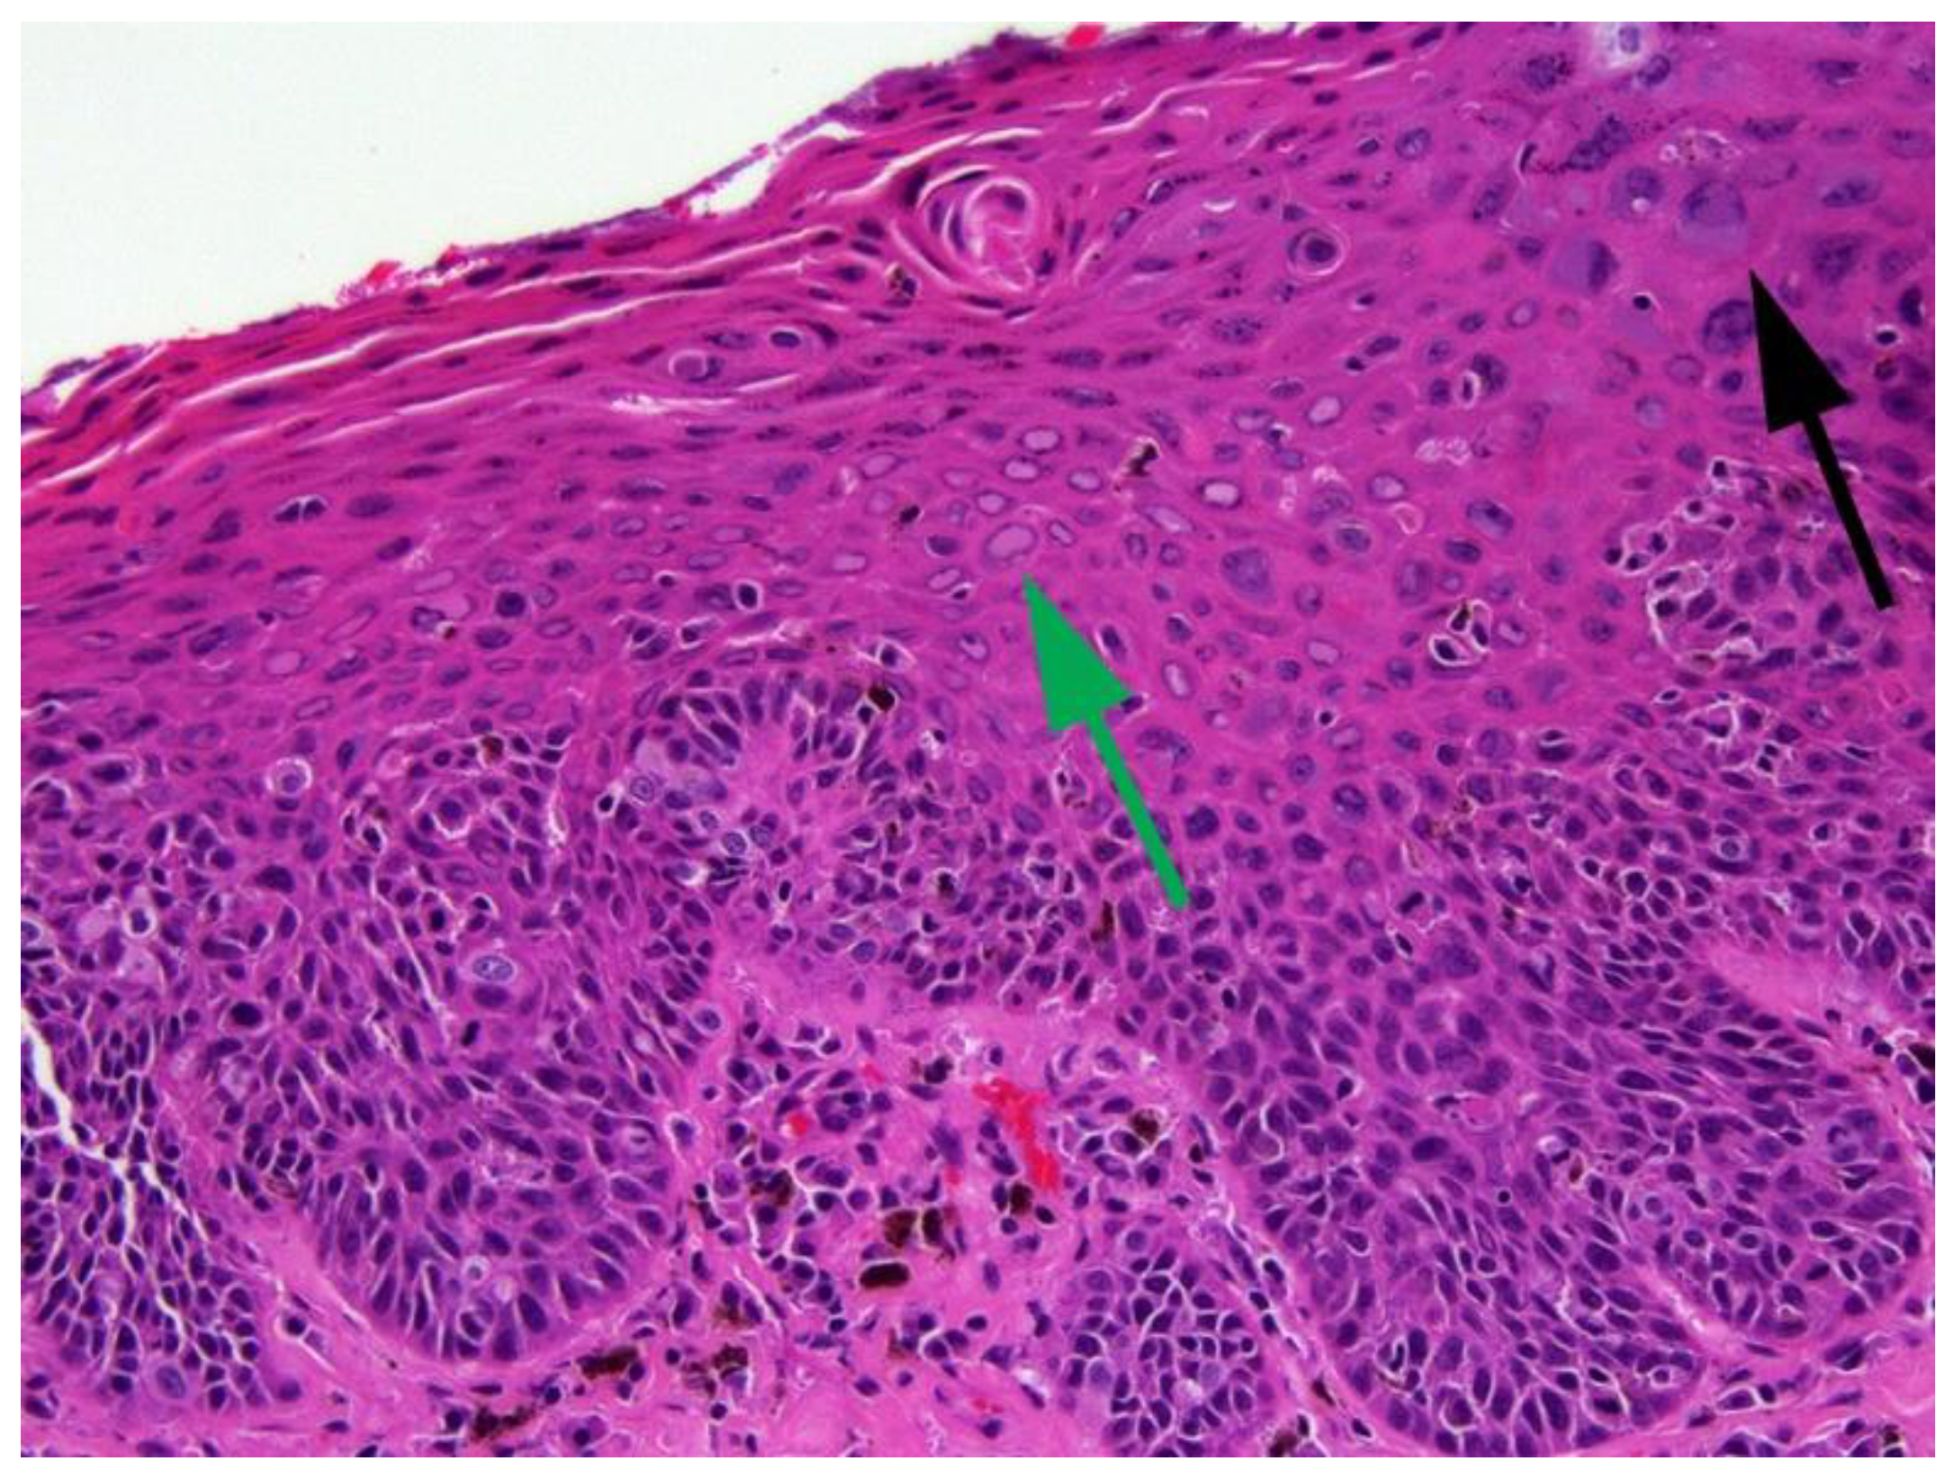

6.2. Canine Viral Cutaneous Plaques

6.3. Papillomavirus-Associated Neoplasia in Dogs

7.3. Papillomavirus-Associated Neoplasia in Cats